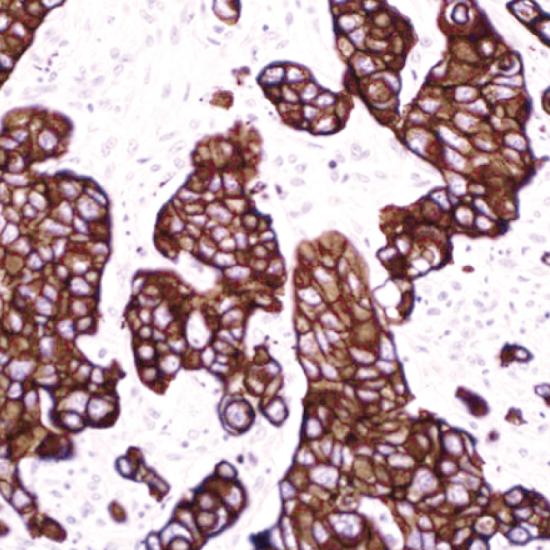

CAM5.2是一種低分子量的細(xì)胞角蛋白,可作為單層上皮細(xì)胞的廣譜標(biāo)記物,定位于細(xì)胞漿。已發(fā)現(xiàn)CAM5.2對(duì)腺上皮和各種腺癌均呈強(qiáng)陽(yáng)性,腺上皮表達(dá)遠(yuǎn)強(qiáng)于復(fù)層鱗狀上皮,大量標(biāo)記結(jié)果顯示鱗狀上皮和尿路上皮不表達(dá)或低表達(dá)。CAM5.2廣泛用于鱗狀上皮和尿路上皮以外的上皮腫瘤標(biāo)記,是腺上皮和各種腺癌最常用的標(biāo)記物,它特異性強(qiáng),敏感性高,是目前認(rèn)為最理想的腺上皮腫瘤標(biāo)記物。